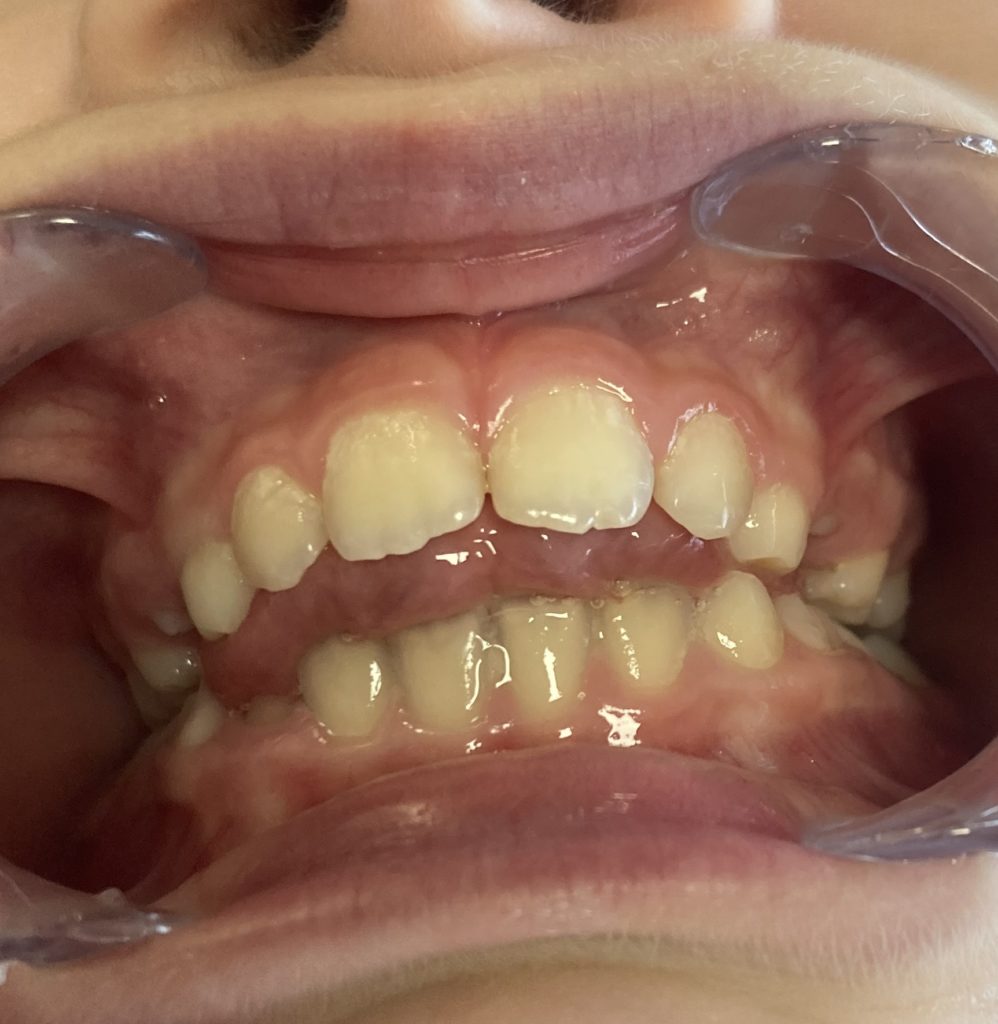

Découvrez en images l’évolution d’une béance liée à une dyspraxie linguale et les bénéfices apportés par une prise en charge adaptée.